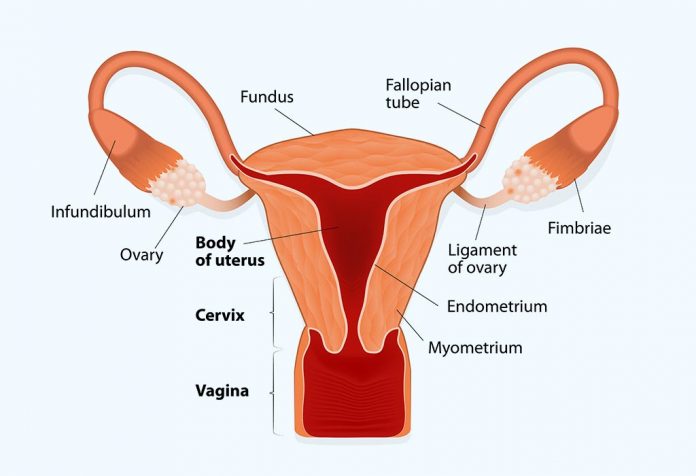

Uterus And The Menstrual Cycle The Uterine Cycle .

Uterine Wall Fluzo Info .